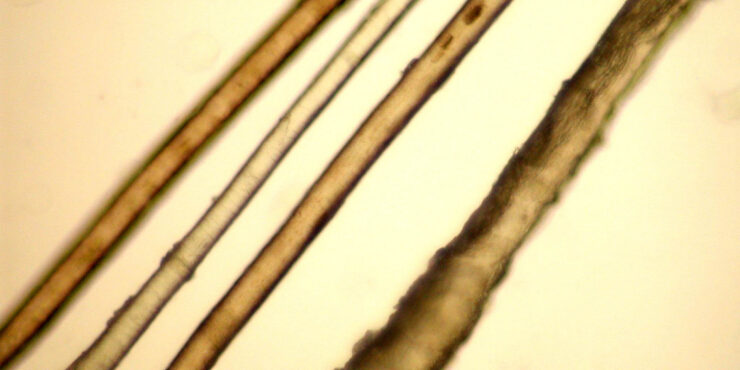

Trichoadenoma =ورم غدي شعري TRICHOADENOMA Trichoadenoma (of Nikolowski) is a rare follicular tumor that some authors consider a neoplastic process, whereas other authors consider it a malformation. These lesions occur most commonly in adults. Clinically, trichoadenoma presents as solitary, slowly growing, grayish nodules measuring up to 1.5 cm in diameter. They are mainly situated […]